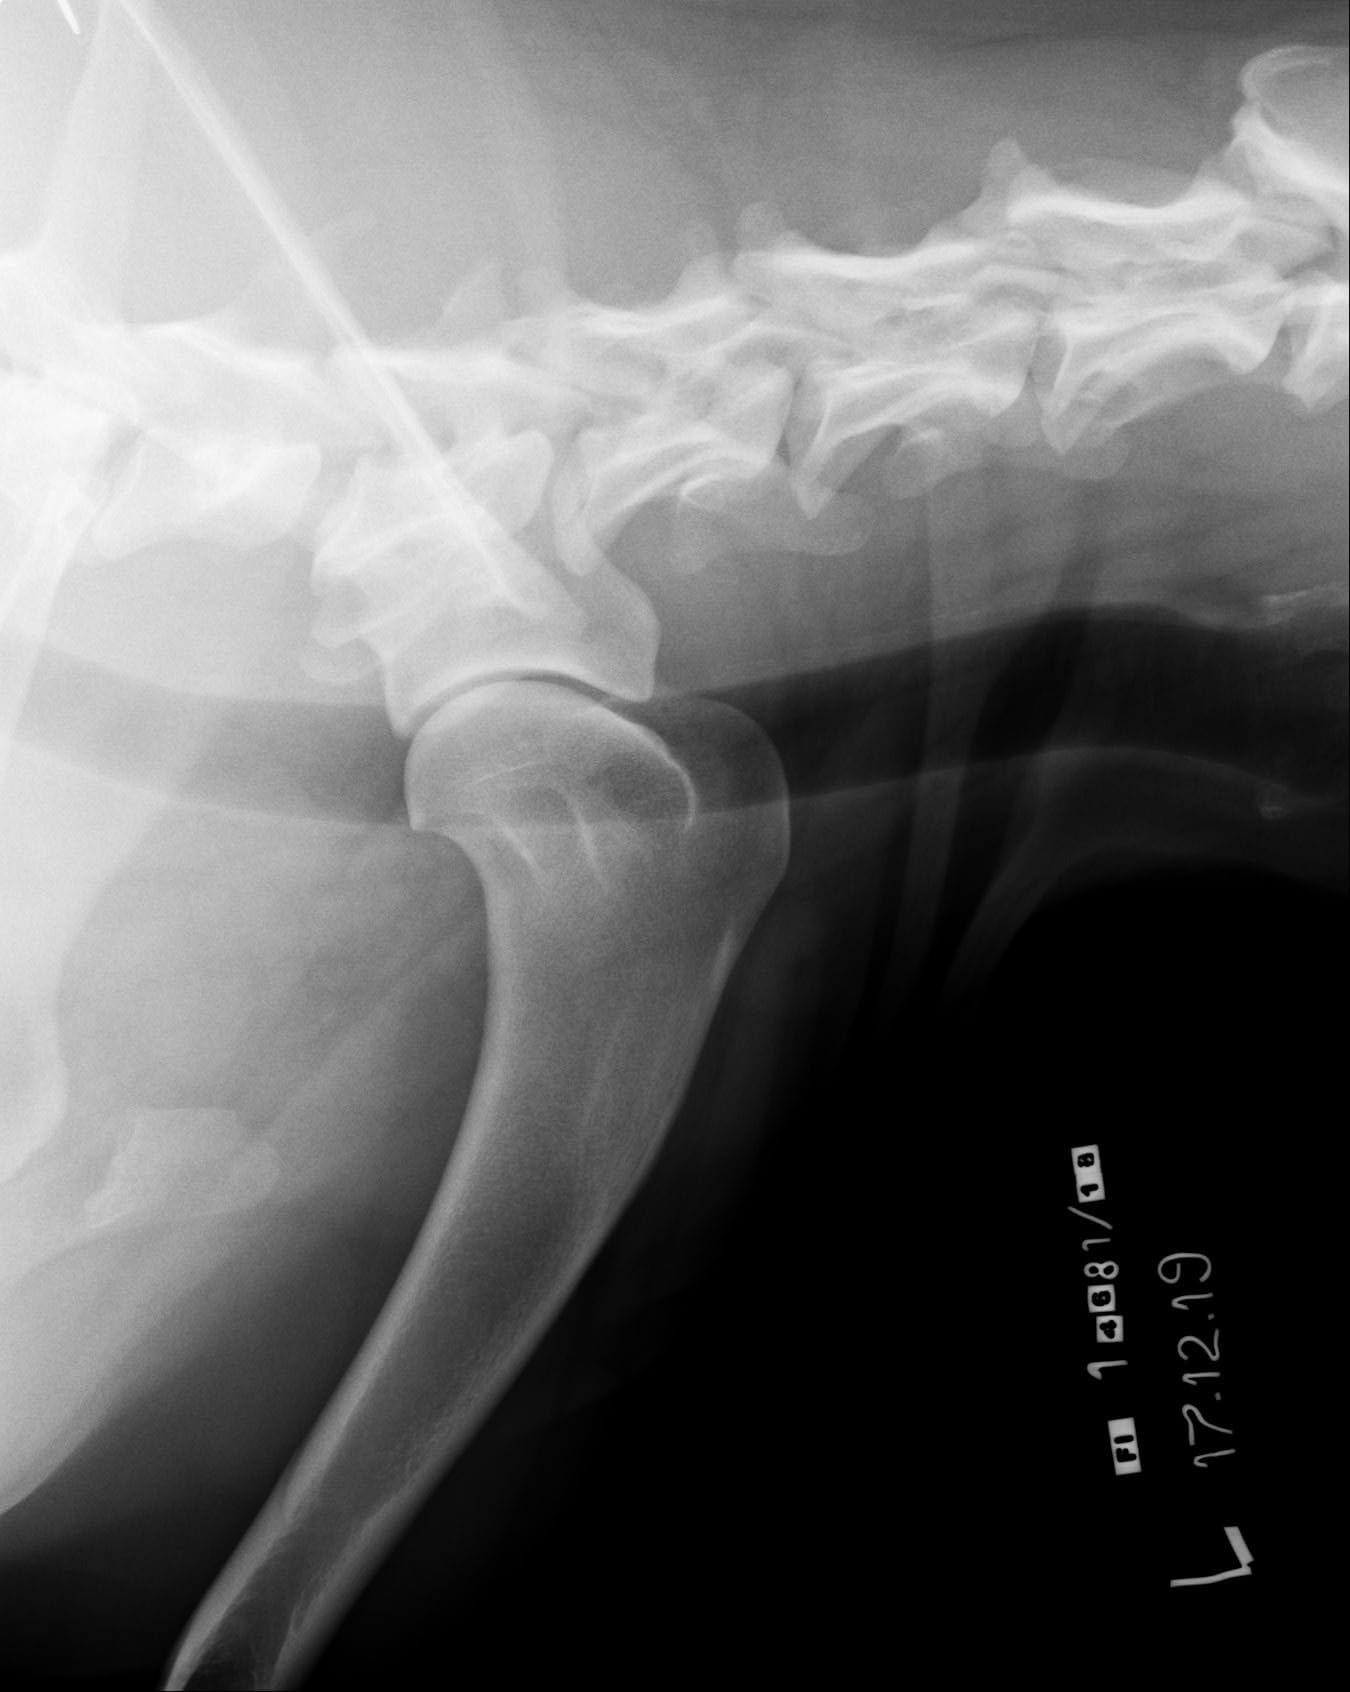

Tähän mennessä Iivo on ollut täysin terve ja Iivo tutkittiin luustoltaan terveeksi joulukuussa 2019. Luonnekuvaukseen (MH, laukausvarma) Iivo osallistui elokuussa 2020.

| Lonkat: | A/A |

| Olat: | Ei todettu/ Ei todettu |